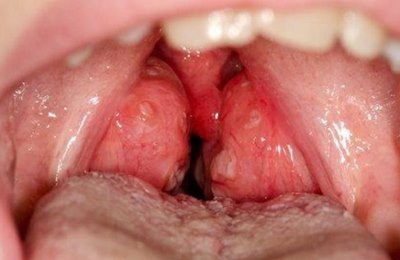

Тонзиллит – воспалительного характера поражение миндалин. При тонзиллите больные жалуются на то, что у них болит горло, больно глотать. Вызывают заболевание бактерии, вирусы и грибы.

Паратонзиллярный абсцесс – поражаются ткани, прилегающие к миндалинам. Боль при этом острая, стреляющая, очень высокой интенсивности. Поражение локализировано с одной стороны, вследствие этого боль интенсивнее или слева, или справа.